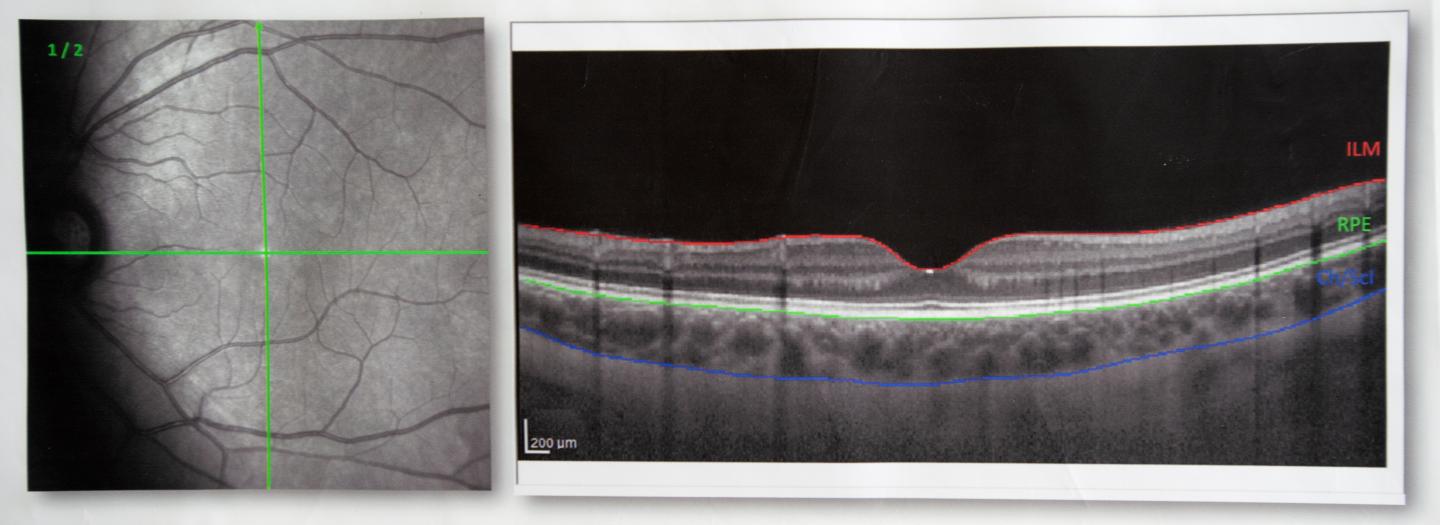

OCT is a common instrument used by optometrists and ophthalmologists. It takes cross-sectional images of the eye which show different tissue layers. These images are high-resolution - about 4 microns; much less than, for example, a human hair, which is about 100 microns thick.

"In our study we looked for a new method of analysing the images and extracting two main tissue layers at the back of the eye, the retina and choroid, with special interest in the choroid," he said.

"The choroid is the area between the retina and the sclera, and it contains the major blood vessels that provide nutrients and oxygen to the eye.

"The standard imaging processing techniques used with OCT define and analyse the retinal tissue layers well, but very few clinical OCT instruments have software that analyses the choroidal tissue.

"So we trained a deep learning network to learn the key features of the images and to accurately and automatically define the boundaries of the choroid and the retina."